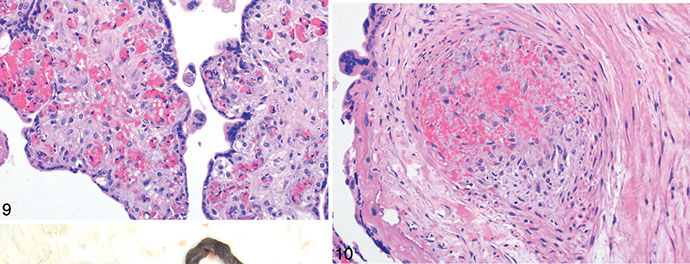

Figure 5. Stem villous vascular luminal obliteration with markedly thickened muscular wall; fibromuscular sclerosis

Figure 6. Nonocclusive intramural fibrin with developing thrombosis [1]